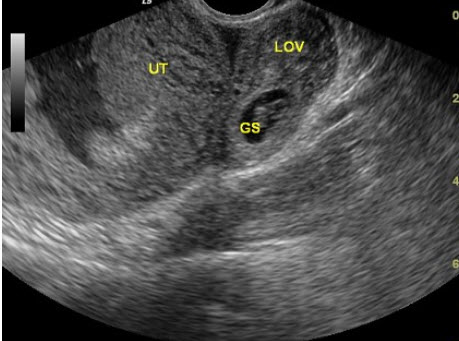

[填空题]

如图,最可能的超声诊断是________。

参考答案与解析: